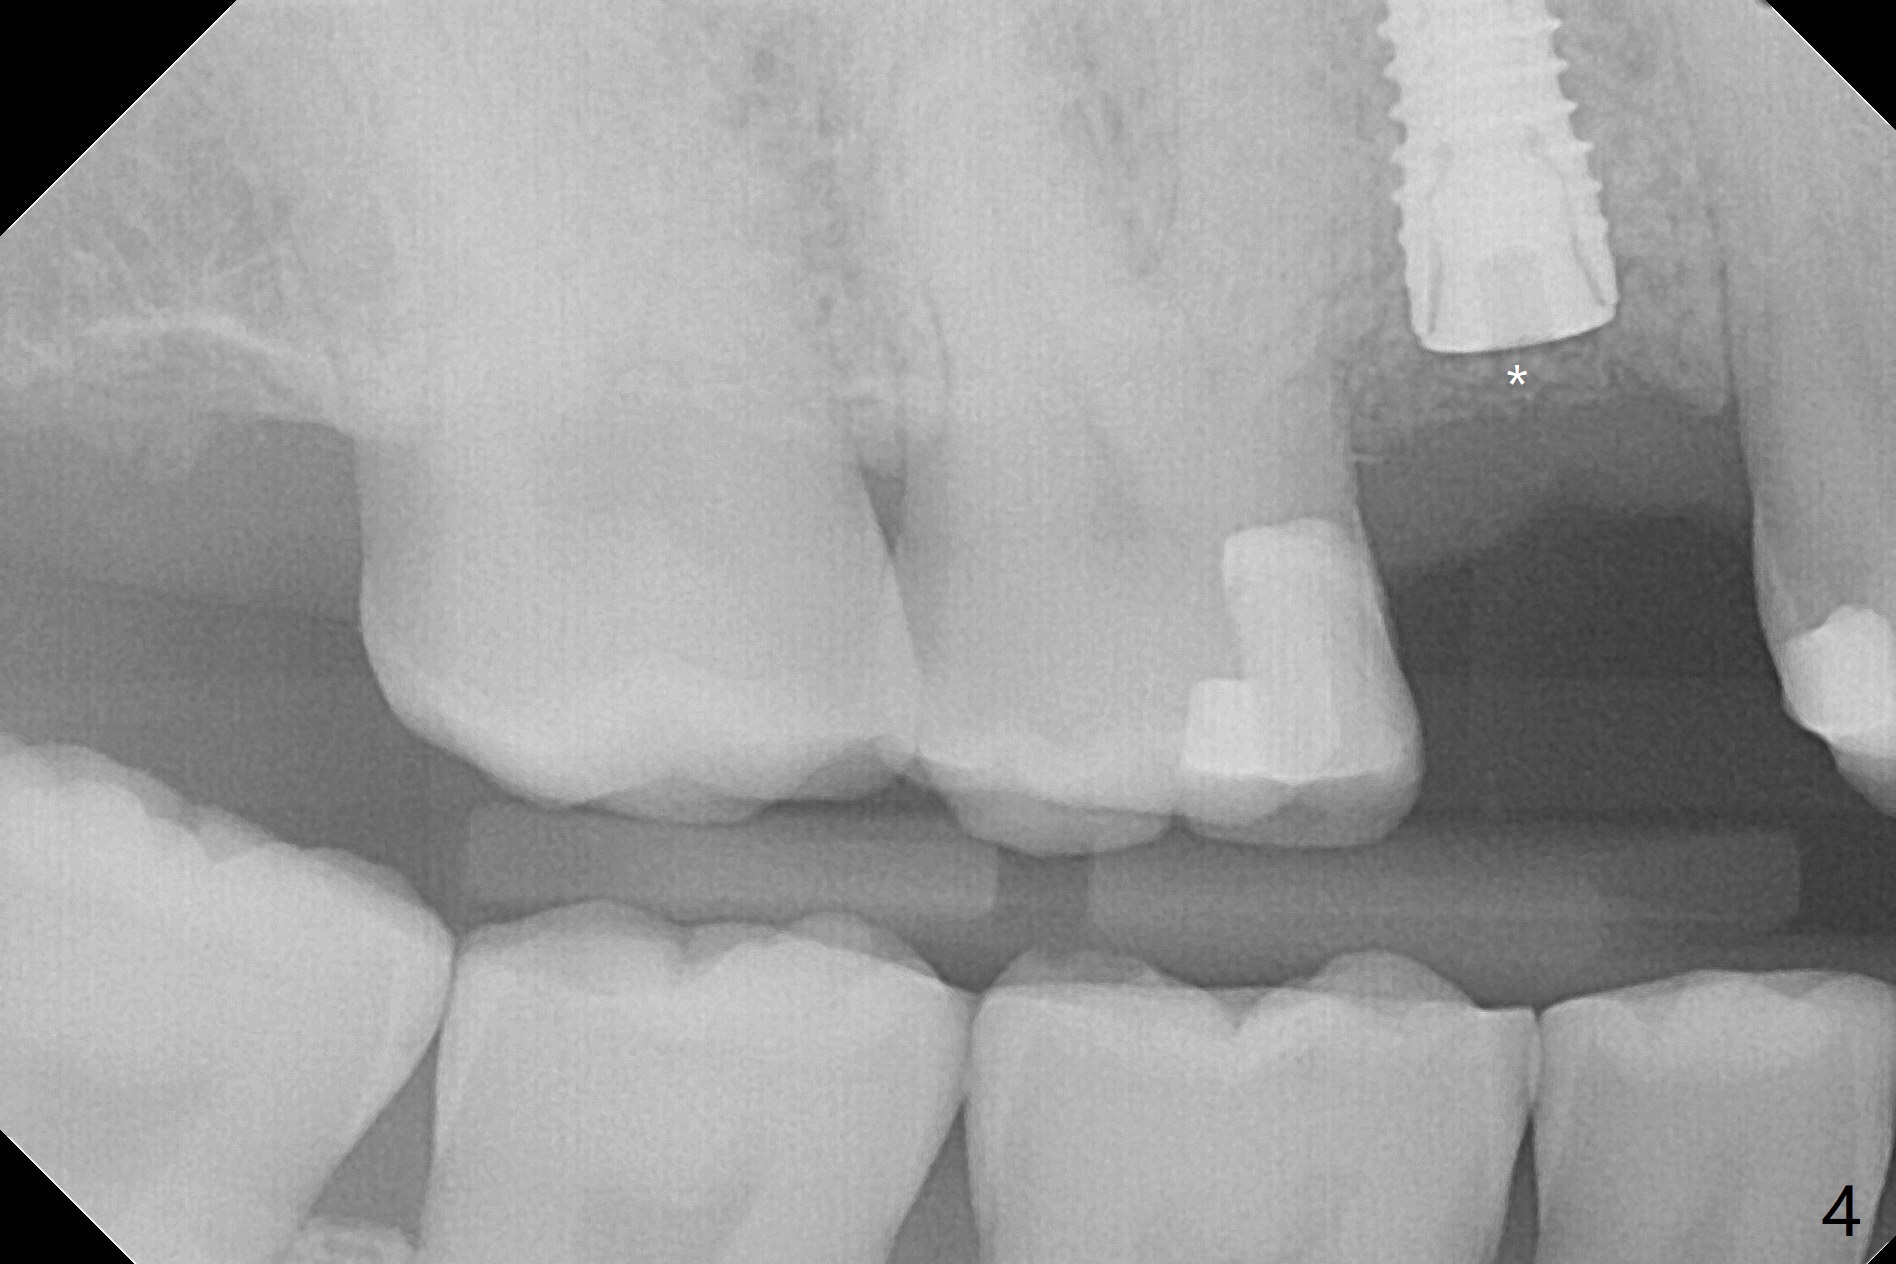

尽管没有任何症状,右上5牙冠粘固后2年5个月,牙冠与基台取出(没有使用扳手,说明基台未完全就位),切开,去除少量肉芽组织,仍然发现植体螺纹暴露(图一),使用一种叫I Brush 钛合金刷子清洁后,放置粘性骨块(图二: S),它坐在牙槽嵴上仿佛非常安稳,多么象马鞍(Saddle)。覆盖一张PRF膜和一小张Cytoplast(不可吸收膜,Osteogenics (company) 图三:箭头),使用PTFE缝线(与Cytoplast同样一种材料)缝合。术后即刻根尖片显示骨粉服服帖帖地坐落在植体和牙槽嵴上(图四:*)。最后覆盖牙周敷料。后者术后十天左右脱落,伤口愈合正常,颊侧瘘道仿佛消失,颊侧骨壁好像不再凹陷了(图五,六)。术后5周,膜已经脱落,缝线撤除后,伤口好像二期愈合,但愿肉芽组织下面骨粉尚未损失太多。术后三个月根尖片显示骨粉减少(图八)。不可吸收膜脱落可能造成骨粉流失。应该做减张缝合。术后4.5个月颊侧骨壁又凹陷(图九:箭头,需要decortication),但是uncover时植体周围都有骨质包绕,术后咬翼片也证明近中,远中骨质接触植体(图十:由于找不到合适愈合基台,直接放置基台和牙冠)。粘固后2.5个月虽然颊侧骨板凹陷,但是没有植体周围炎迹象(图十一)。